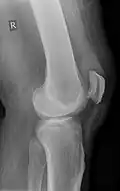

Quadriceps tendon rupture in plain X-ray: Incomplete rupture with haematoma in tendon. -